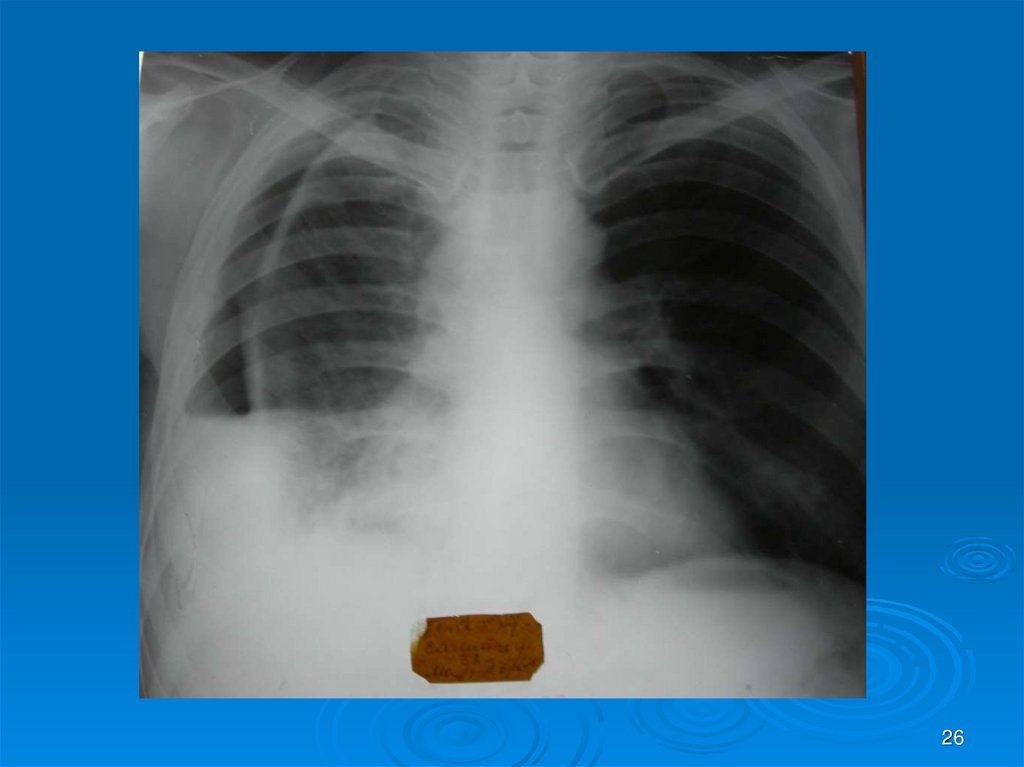

26.

26